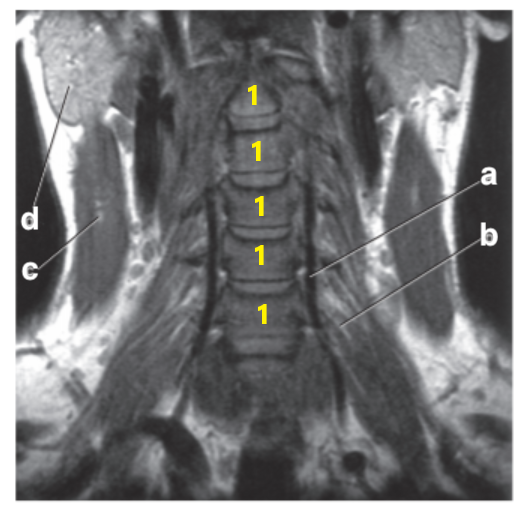

What imaging plane is this?

coronal

Cervical Spinal cord